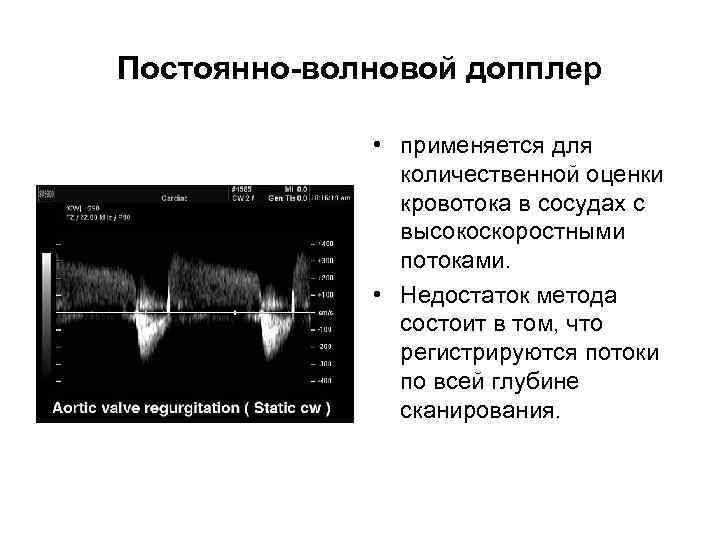

Постоянно-волновой допплер • применяется для количественной оценки кровотока в сосудах c высокоскоростными потоками. • Недостаток метода состоит в том, что регистрируются потоки по всей глубине сканирования.

Постоянно-волновой допплер • применяется для количественной оценки кровотока в сосудах c высокоскоростными потоками. • Недостаток метода состоит в том, что регистрируются потоки по всей глубине сканирования.